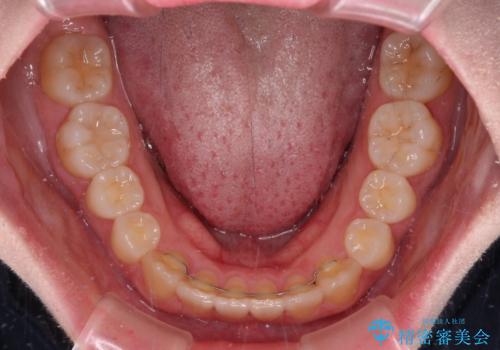

ディープバイトをインビザライン矯正で改善

インビザラインを用いて、前歯の叢生を解消するとともに、ディープバイトを改善していくこととしました。

上顎に乳歯が左右1本ずつ残っていたため、若干咬み合わせに不具合が残りましたが、強い咬合力の原因であったディープバイトをしっかりと改善することができました。